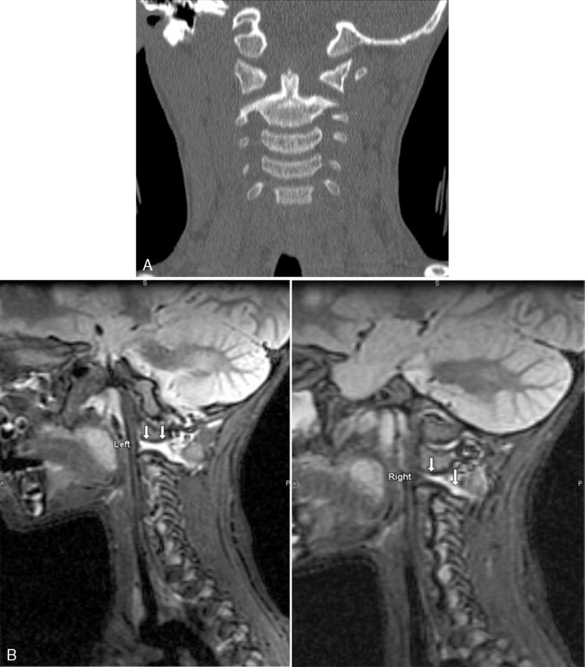

Spinal cord injuries are less common in children than in adults. When these injuries occur in children, they are generally associated with motor vehicle-related crashes, falls, and inflicted head trauma and can result in injuries of the upper or lower cervical spine (Fig. 19-1).4

image

Fig. 19-1 Cervical spine injury. Lateral cervical spine radiograph indicating cervical spine injury. A, Cervical spine radiograph of a toddler demonstrating wide separation between the first and second cervical vertebrae, consistent with complete cervical spine injury at the level of C1 to C2. Note the anterior displacement of the nasogastric tube (arrow) indicating anterior displacement of the esophagus (which should lie just anterior to the vertebrae) caused by edema at the site of the spinal cord injury. This child was intubated, but the endotracheal tube is not visible because it is not radiopaque. B, Normal anatomy of the cervical spine in a toddler. Note the horizontal articulation of the vertebrae, which increases the mobility of the upper cervical spine in this age group.

(A. Radiograph courtesy of John B. Pietsch, Nashville, TN. B. Illustration from Riviello JJ, et al: Delayed cervical central cord syndrome after trivial trauma. Pediatr Emerg Care 6:116, 1990. Williams and Wilkins.)